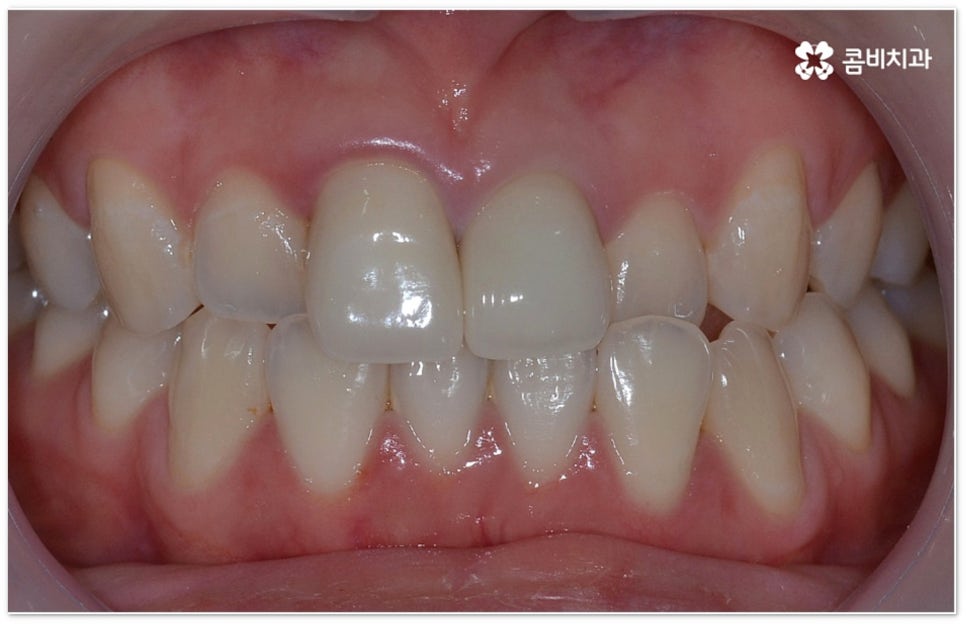

희고 가지런한 치아를 드러내며 환하게 웃는 사람을 보면 자기도 모르게 호감이 가곤하죠, 이처럼 대인 관계에서 치아는 좋은 인상을 만드는 데 심미적으로 큰 역할을 할 뿐 아니라 식사시 음식물을 저작하고 발음을 제대로 하는 데도 많은 도움을 주기 때문에 만약 타고난 치아가 삐뚤어졌거나 위아래 교합이 제대로 맞지 않는다면 이를 기능적 심미적으로 바로잡아 주기 위해서 치아 교정 치료를 고려해 볼 수 있습니다.

요즘 가장 많이 쓰이는 치아교정장치 인 클리피씨는 치아 색상의 세라믹 브라켓을 이용하기 때문에 심미성도 뛰어나고 자가결찰방식을 이용하여 보다 적은 힘으로 지속적이고 부드러운 치아 이동을 할 수 있도록 고안된 장치이므로 통증을 줄여줄 뿐 아니라 보통 2년 남짓 걸렸던 전체 교정 기간 역시 6개월 정도 감소시켜 줄 수 있습니다. 환자분들의 상황에 따라 내원 횟수 역시 줄일 수 있기 때문에 업무가 많이 바쁜 직장인분들의 경우에도 이용할 수 있다는 장점을 가지고 있어요.

부정교합을 개선할 때 교합이 어긋난 정도가 심하고 구조적인 원인이 커서 부분 교정이 아닌 전체 교정이 필요한 케이스인 경우라고 해도 말씀드렸던 클리피씨 교정 장치 또는 보다 심미성을 강조한 치아교정장치 들의 도움을 통해 다른 사람과 얘기를 하거나 음식을 먹을 때 브라켓이 두드러지게 드러나는 부담을 줄일 수 있으니 설측교정, 콤비교정, 투명교정, 인비절라인 등에 대해서 한 번 알아보시고 각자에게 맞는 방법으로 교정 치료를 시작해 보시길 권유드리고 있어요.

특히 투명교정의 경우 겉에서 봤을 때 교정하는 티가 거의 나지 않는 특수 플라스틱을 이용한 장치이기 때문에 심미적으로 보다 만족스러울 수 있는데요. 브라켓이나 와이어가 없으므로 이물감이 적고 이로 인해 입 안 쪽에 상처가 발생하지도 않게 되며, 발음도 명확하게 구사할 수 있다는 장점 또한 가지고 있어요. 식사할 때 빼놨다가 양치 후 닦아서 다시 끼면 되기 때문에 관리할 때도 용이하지만 이러한 탈착식 장치는 착용하는 시간을 어느 정도 확보해야 보다 효과적인 치료 결과가 나올 수 있다는 점을 명심하고 환자분들 스스로 정해진 시간 이상 잘 착용해 주실 필요가 있습니다. 치아가 얼마나 이동했는가를 보고 환자분들의 상황에 맞게 그때 그때 본을 떠서 치아교정장치 를 제작하기 때문에 섬세한 진행이 가능하다는 장점이 있으나 빠르고 정확하게 대응을 하기 위해서 다양한 케이스를 다뤄보신 노하우가 있는 선생님과 함께 하시는 것이 무엇보다 중요하다는 점 또한 잘 알아두시면 좋을 거예요.